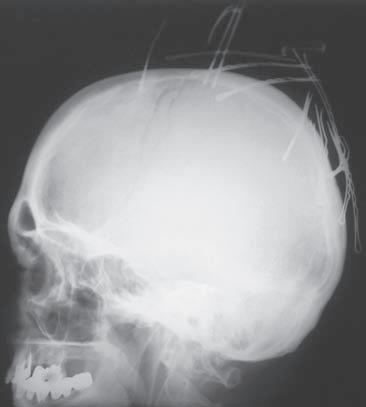

O br. 1. 1 Princip d vou proje k cí. S k iagram l e bk y v pře d oza d ní proje k ci (a). Spon k y do vlasů ne j sou lokalizovány intrakraniálně, ale na temeni ve vlasech, j ak j e zře j mé ze skiagramu lebky v boční projekci (b)

P ouze jedna projekce ke správnému vy h odnocení diagnostické informace nes tačí (obr. 1.1). Jde totiž jen o dvojrozměrn ý obraz trojrozměrného objektu, RTG obraz je ted y sumační. Snímkování anatomick ý ch struktur ve dvou na s ebe kolmýc h projekcíc h poskytuje informaci o prostorovém uložení zobrazov an ý ch struktur. Druhá projekce může zobrazit patolo g ick ý proces, kter ý není v iditeln ý v první projekci (obr. 1.2). K dostatečnému zobrazení někter ý ch anatomickýc h struktur (např. člunková kost, C-T h přec h od) je někdy nutné d op l n i t i spec i á l ní pro j e k ce (v i z j e d not li vé k ap i to ly ) .